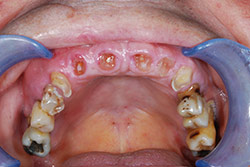

I denti irrecuperabili dell'arcata superiore ed inferiore del paziente di anni 65

sono stati sostituiti da 10 impianti, cioè protesi radicolari endo-ossee che sostengono le protesi fisse superiore ed inferiore.